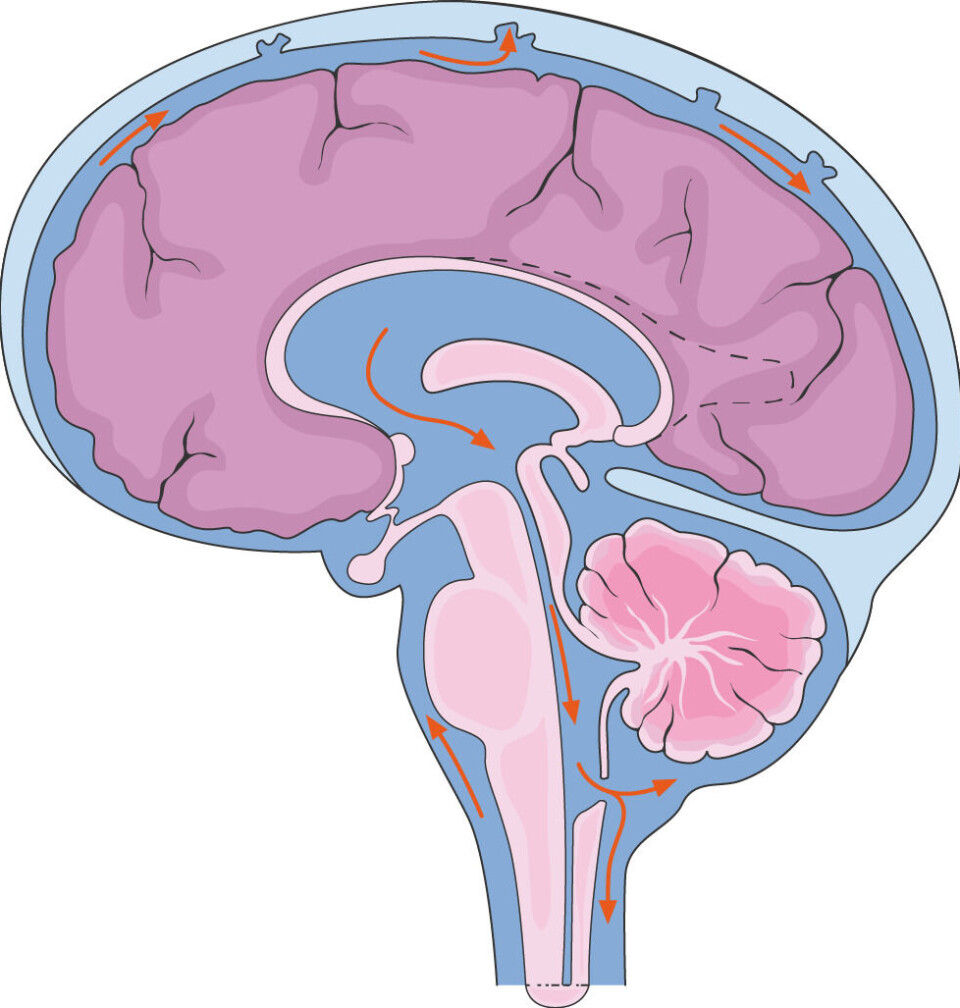

Participants in the new study had a contrast agent injected into their spinal cords, where it mixed with the clear cerebrospinal fluid.

This fluid flows up to the skull, surrounds the brain, and fills the cavities.

According to classical knowledge, the fluid surrounding the brain flows around in a space between two meninges.

The fourth membrane, on the other hand, divides this fluid-filled space in two, according to Nedergaard and colleagues.

The implications of this are unclear, but the division might allow fresh cerebrospinal fluid to penetrate the brain more easily.

So there may be a tube-like structure surrounding the blood vessels going into the brain.

Fresh cerebrospinal fluid can hitch a ride with the blood vessels in this tube into the brain, the Norwegian researchers believe.

The same can happen when the contrast agent is injected into the spine.

This means that the dyed cerebrospinal fluid reaches the blood vessels faster, which are centrally located in the fluid-filled space around the brain.